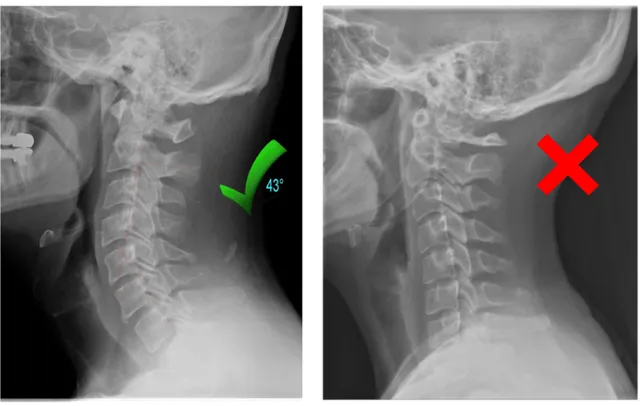

2. Dein Nacken hat seine natürliche Krümmung verloren

Jahrelanges Nach-unten-Schauen auf das Smartphone, langes Arbeiten am Schreibtisch und eine ungünstige Schlafhaltung können die natürliche Krümmung deiner Halswirbelsäule abflachen.

Die Folge sind zusammengedrückte Wirbel, eingeklemmte Nerven und chronische Schmerzen, die weder durch Massagen noch durch herkömmliche Kissen dauerhaft behoben werden können.

Der kritische Punkt: Sobald deine zervikale Krümmung verloren ist, kommt sie nicht von selbst zurück. Du brauchst eine anhaltende Dehnung des Nacken im Schlaf.